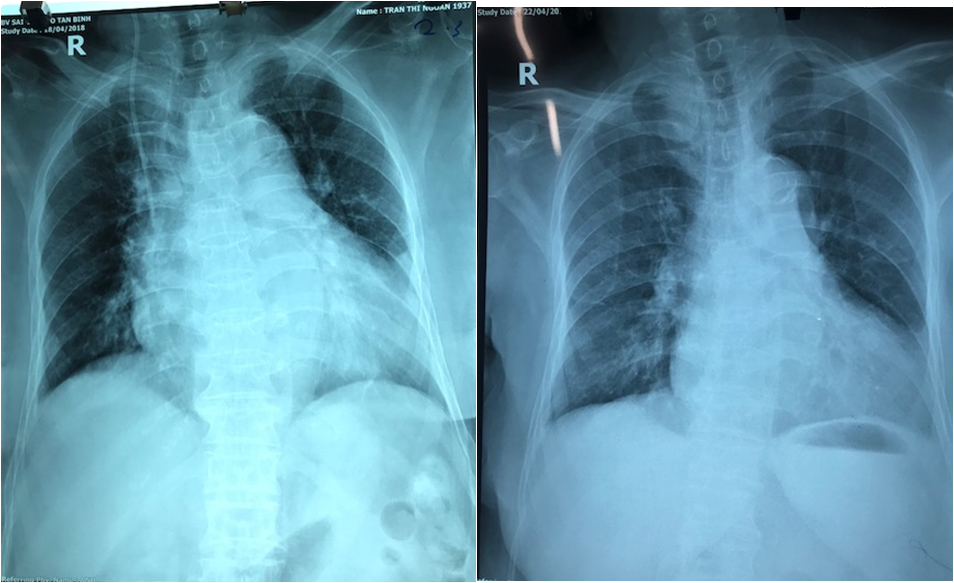

Hình ảnh X-Quang cho thấy tình trạng suy tim, bội nhiễm phổi nặng (Ảnh: BVCC)

Trong 2 ngày đầu được chăm sóc tích cực 24/24h tại khu nội trú bệnh viện, tình trạng sức khỏe của bệnh nhân ổn định hơn, các chỉ số xét nghiệm giảm đáng kể. Tuy vậy, người bệnh vẫn còn sốt cao, suy tim bội nhiễm phổi nặng vẫn cần phải thực hiện phẫu thuật nếu không thì bà sẽ chết do biến chứng này.